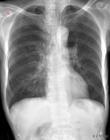

間質性肺病(Interstitial lung Disease,簡稱ILD) 是以彌漫性肺實質、肺泡炎和間質纖維化為病理基本改變,以活動性呼吸困難、X 線胸片示彌漫陰影、限制性通氣障礙、彌散功...